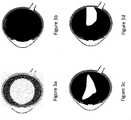

- the distribution of the drug in the vitreous body resulting from the set of equations is shown in Figure 3d .

- FIG. 3a A simplified model of the drug flow in the vitreous body is shown in Figure 3a , for which only an isotropic diffusion is assumed.

- Figure 3b the vitreous body contains collagen fibers creating a meshwork with a heterogeneous structure that determines an anisotropic diffusion.

- Figure 3c The result of an anisotropic ansatz is shown in Figure 3c .

- the flow of the drug is not only due to diffusion but also to advection, since the vitreous body is made up of water up to 98%.

- the advection is affected by gravity and Figure 3d shows the drug distribution once the gravity effect is also taken into account.